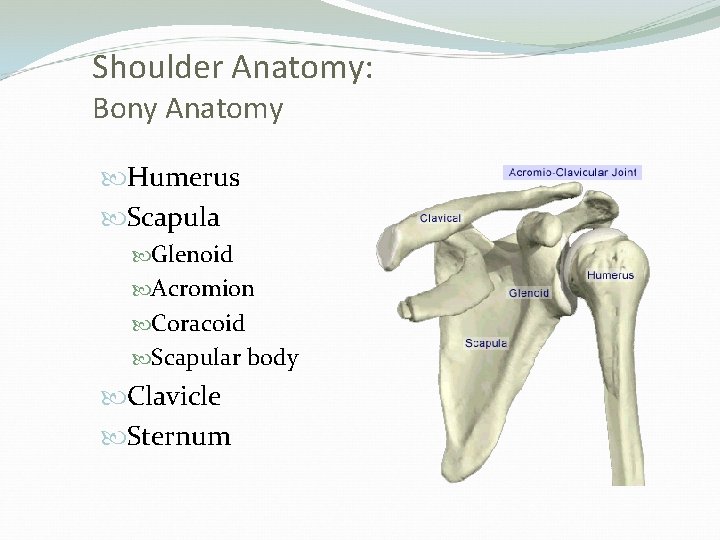

Shoulder Anatomy: Bony Anatomy Humerus Scapula Glenoid Acromion Coracoid Scapular body Clavicle Sternum

Bones Humerus. Scapula (acromin): Type I : flat Type II: curved Type III: hooked Clavicle

Joints Glenohumeral joint: the main joint Acromioclavicular (AC) joint Sternoclavicular (SC) joint Scapulothoracic joint